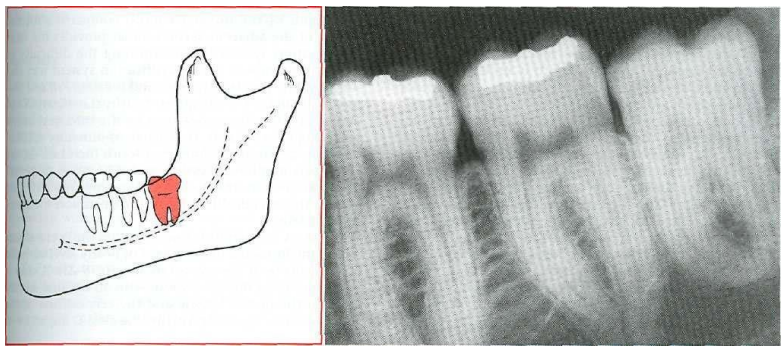

3- Horizontal 14

In a severe mesial inclination the impacted tooth is horizontal the longitudinal axis of the third molar tooth forming 90 degree angle with the longitudinal axis of the second molar tooth

Fig.3: horizontal impaction ' From Contemporary Oral and Maxillofacial Surgery, chapter 9 Larry J. Peterson. Principles of management of impacted tooth p 194